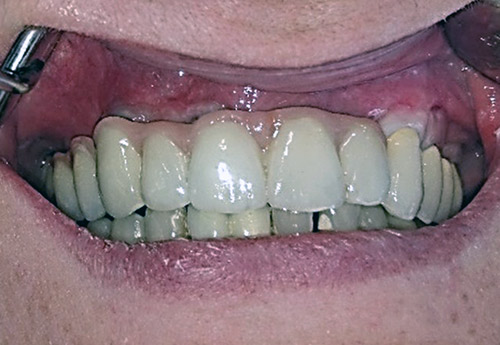

3. PHASE – prosthetic fabrication of temporary crown on implant